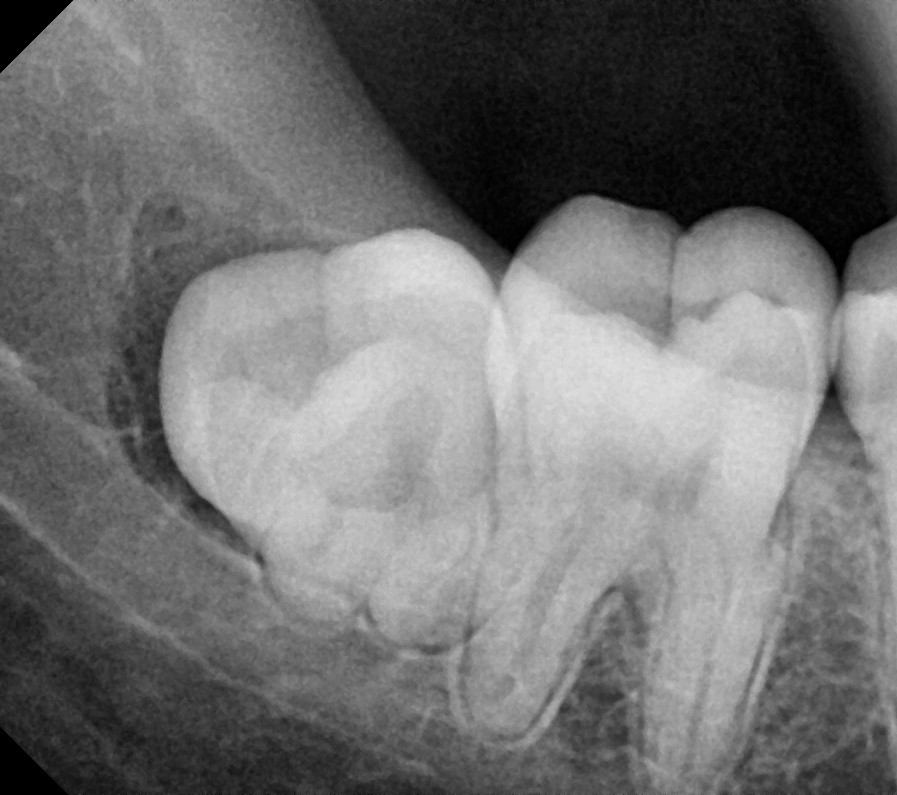

Lower 3rd Molar

After After

Before Before